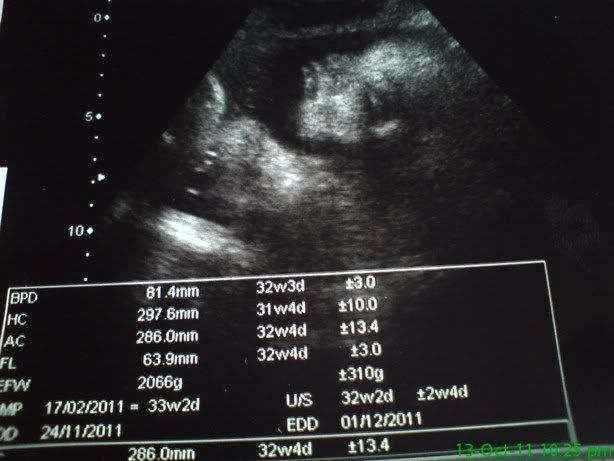

年尾的天气怪怪的,还是早点把衣物洗好,比较安心。34周了,待产包要随身携带了! |